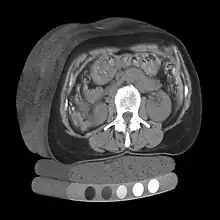

Tomography is imaging by sections or sectioning that uses any kind of penetrating wave. The method is used in radiology, archaeology, biology, atmospheric science, geophysics, oceanography, plasma physics, materials science, cosmochemistry, astrophysics, quantum information, and other areas of science. The word tomography is derived from Ancient Greek τόμος tomos, "slice, section" and γράφω graphō, "to write" or, in this context as well, "to describe." A device used in tomography is called a tomograph, while the image produced is a tomogram.

| X-ray computed tomography | X-ray | CT, CATScan | 1971 |

Volume rendering is a set of techniques used to display a 2D projection of a 3D discretely sampled data set, typically a 3D scalar field. A typical 3D data set is a group of 2D slice images acquired, for example, by a CT, MRI, or MicroCT scanner. These are usually acquired in a regular pattern (e.g., one slice every millimeter) and usually have a regular number of image pixels in a regular pattern. This is an example of a regular volumetric grid, with each volume element, or voxel represented by a single value that is obtained by sampling the immediate area surrounding the voxel.